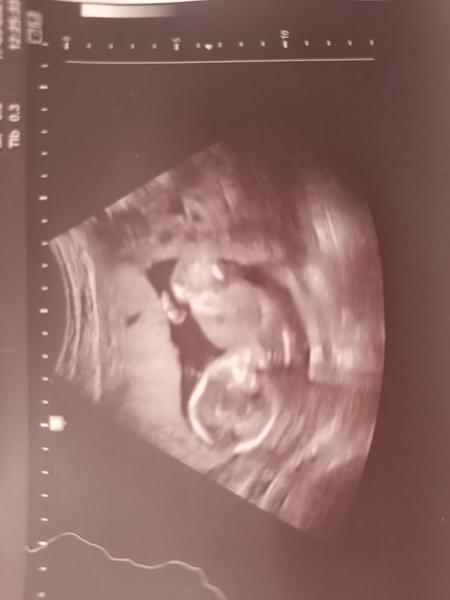

Ahoj holky,

tak dneska jsme byli na ultrazvuku v 20.tt. Bylo tam vidět tohle ...No paní doktorka nám řekla, že by zatím nedělala závěry, co to bude a že máme počkat.

Jasně, že počkáme na doktora, ale jsem strašně zvědavá. A hlavně...asi tam vidím pindíka 😁 Tak na to prosím taky koukněte, jestli jsem si to nevsugerovala 😁